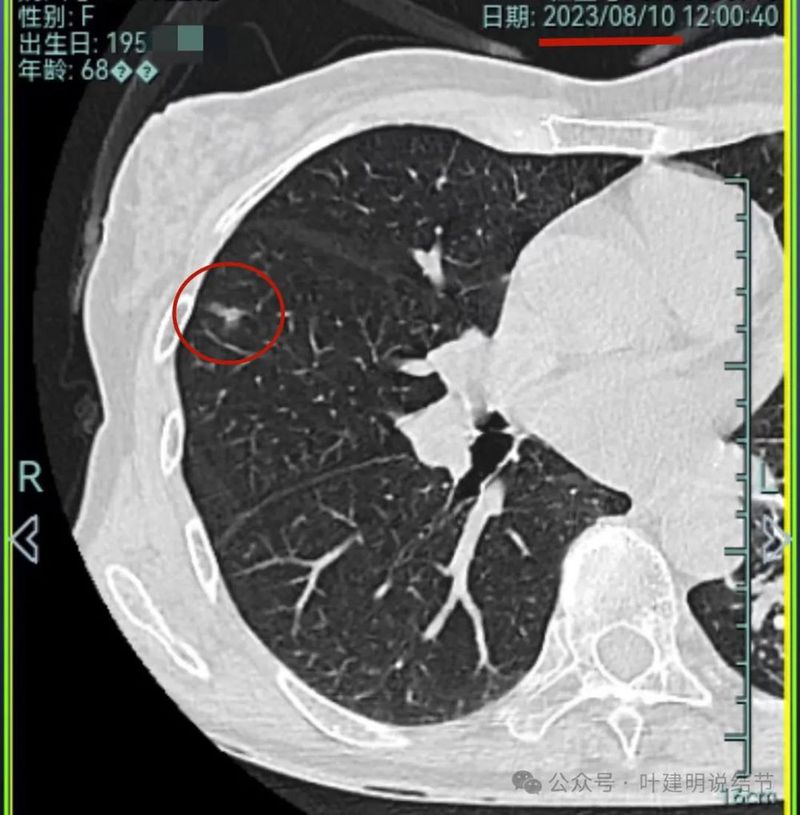

再看2023年8月的影像:

病灶1没什么进展。

病灶2与前相仿。

病灶3仍混合密度,说不上显著进展。

病灶4 仍是钙化的,大小也没有进展。

病灶5较前密度又有增高,贴着叶间裂,整体轮廓显得较之前清楚些,更符合恶性表现了,而且应该是浸润性腺癌。

病灶6与前相仿。